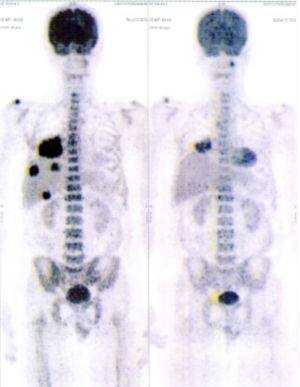

CASE NO: 3 (PROSTATE CANCER)

A middle-aged man with castration resistant prostate cancer, having failed all currently available cancer treatment, was very weak, and getting worse every day. The PET/CT scan showed he had massive bone metastases. After a few treatment, all the bone metastases went into remission. About 6 months later, he is still in remission.

CASE NO: 4 (PROSTATE CANCER)

A middle-aged man with castration resistant prostate cancer and massive bone metastases, failed all currently available cancer treatment, including with the new and expensive drug XTANDI. After a few treatment, most of the bone metastases went into remission, and the remaining ones are less active. Treatment will continue. Cases no: 3 and 4 show that terminal prostate cancer today can be cured with our new cancer treatment.